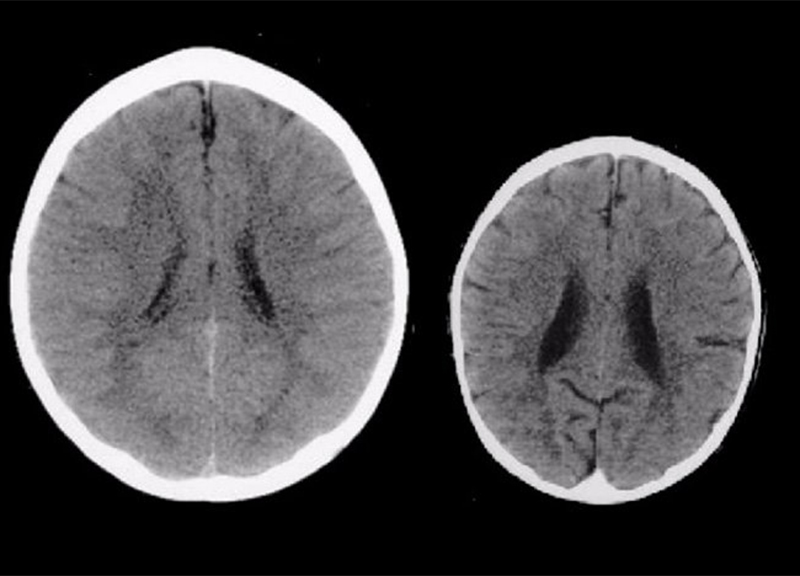

Il confronto tra le Tac al cervello di due bambini hanno rivelato la presenza di traumi infantili dovuti a abusi o negligenze

La scansione a sinistra è di un bambino di tre anni, cresciuto in un ambiente amorevole, mentre quella sulla destra è di un bambino che ha subito traumi emotivi ed è stato vittima di negligenze.

Le immagini mostrano la scioccante realtà di come gli abusi sull’infanzia possono modificare lo sviluppo del cervello. Le scansioni sono state condivise dal professor Bruce Perry, direttore del reparto psichiatria del Texas Children’s Hospital. Il professore spiega come il bambino nella scansione destra soffre di 'grave negligenza di deprivazione-sensoriale” e di conseguenza il cervello è molto più piccolo e ha una struttura molto più confusa.

"Queste immagini illustrano l'impatto negativo dell'abbandono sul cervello in via di sviluppo. Nella Tac al cervello di sinistra c’è un'immagine di un bambino di tre anni sano con una dimensione media della testa. L'immagine a destra è di un bambino di tre anni che soffre di una grave negligenza di deprivazione-sensoriale. Il cervello di questo bambino è notevolmente più piccolo della media e presenta ventricoli allargati e un’atrofia corticale. L'atrofia corticale è spesso associata a persone anziane che soffrono di Alzheimer.”